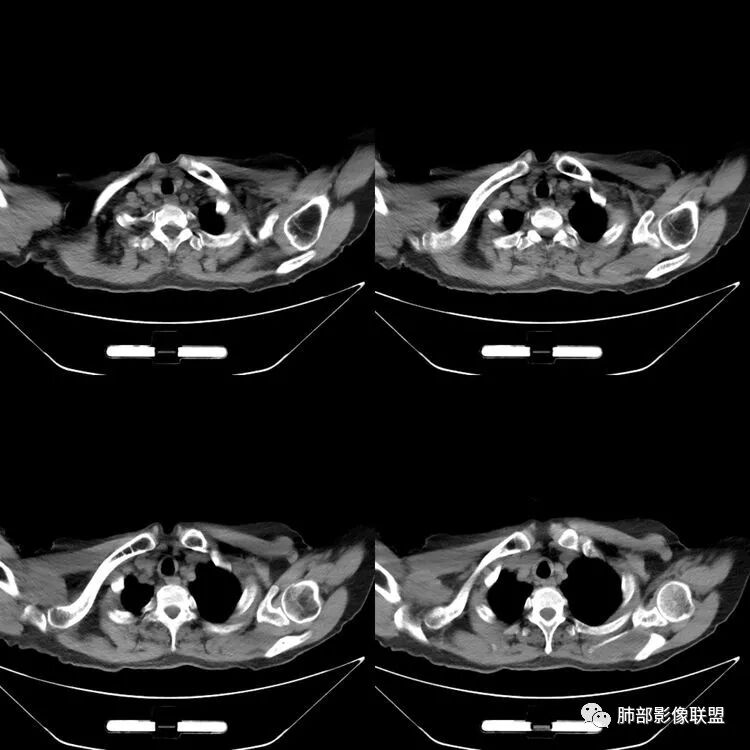

患者,女,64岁,反复咳嗽、咳痰、胸闷10年,加重2周患者10余年来每当受凉感冒出现咳嗽、咳痰、胸闷,有时痰中带血,输液治疗(具体不详)可好转。既往有声带肥厚手术病史。CT示气管、主支气管及分支支气管管壁弥漫性增厚累及膜部,局部伴钙化,管腔狭窄,考虑淀粉样变性

患者,女,64岁,反复咳嗽、咳痰、胸闷10年,加重2周。气管支气管及两肺下叶 支气管弥漫性的环状增厚,管腔扩张,管腔感觉比较松弛。第一感觉,气管支气管淀粉样变。鉴别诊断,1、支气管内膜结核,肺内散在一些支气管的播散病灶,粟粒结节为主,形态比较单一。2、复发性的多软骨炎,就得了解一下其他部位,有没有多个部位的软骨炎。这个病人右侧胸廓缩小,升主动脉明显的扩张,其横径明显的超过了降主动脉。

征象很明确

弥漫支气管壁增厚,膜部受累

声带肥厚——受累

隐约见钙化

南边:肺部有肺气肿支气管腔狭窄淀粉样变性?复发性多软骨炎?血管炎?慢支?结核?曲霉菌?南边:一般还是淀粉样变性与复发性多软骨炎鉴别其次就是支气管骨化症,但是骨化下朝上,且壁结节状钙化明显,本例不太支持。至于结核、曲霉菌?1.结核,一般不会这么广泛,支气管壁狭窄后扩张2.曲霉菌可以这么广泛,但是支气管壁管腔扩张,而且附近脂肪间隙有炎性反应,不太支持;3.血管炎,一般合并肺内有病灶,但是声带受累,放待排;4.软骨炎一般全身受累,例如耳廓等;而且膜部不受累,不太支持;倾向于淀粉样变性;淀粉分很多型,气管支气管是最常见的。尘缘:影像上生理性钙化与支气管骨化无法区别,镜检也不好鉴别,需要依赖活检,看粘膜中是否合并炎性改变(淋巴细胞,组织细胞等炎性细胞侵润)来鉴别Coke with ice:经常看到的这种是老年性肺改变,又称年龄相关肺改变。气管和支气管弥漫性软骨钙化,常见老年女性。尘缘:支气管骨化症很罕见的,所以绝大多数还是生理性钙化。对于老年人,无临床症状的钙化,还是基本上都是生理性钙化,无临床意义。大雄:如果管壁钙化伴明显增厚 影像还是提示一下建议支气管镜稳妥些

病理结果:肺淀粉样变

气管支气管淀粉样变性

三、影像表现

1.气管支气管型

①气管支气管壁增厚,形成粘膜下斑块与结节

②管腔广泛狭窄、闭塞

③管壁钙化

④膜部受累(具有重要鉴别意义)